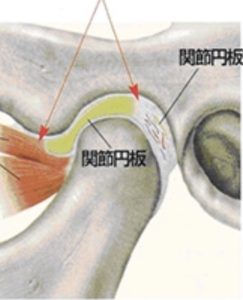

顎関節の内部には関節円板があり、これが軸と軸受けとの間にあります。下顎頭は口を開けるときに前方に移動します。その時関節円板は一緒に移動して仮の軸受となります。

関節円板が前方にズレていて、変形してる状態。

口を開けると、下顎頭が変形した関節円板に引っかかる。

引っ掛かりが外れて下顎頭がさらに前に出るときに、カックンと音が鳴る。